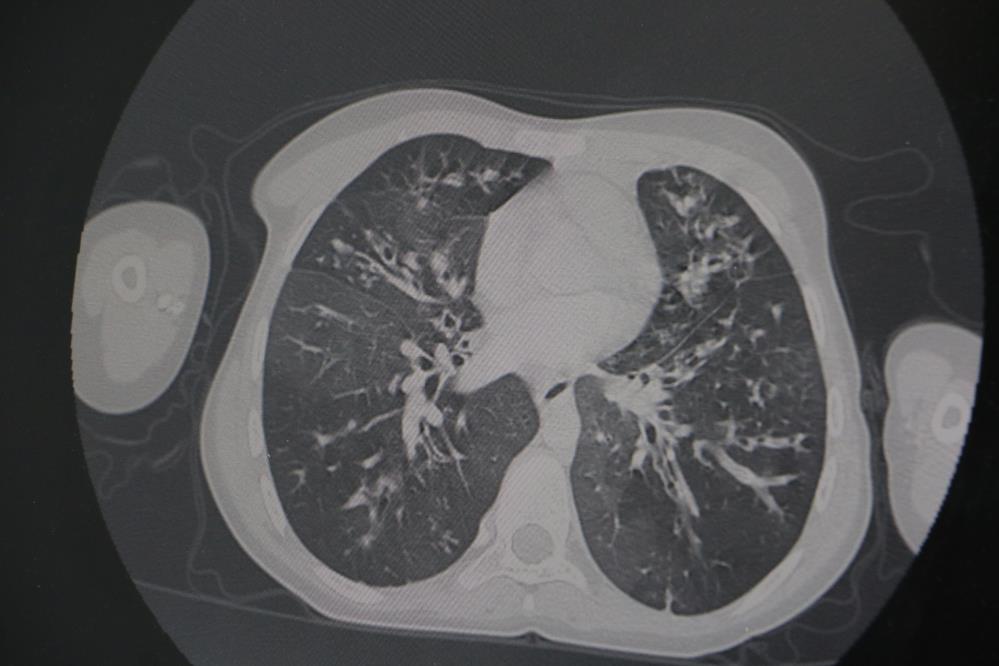

Kistikfibrozis hastalığında erken tanı önemli

"Erken tanıyla kanser hastalarının yüzde 90'ı iyileşiyor"